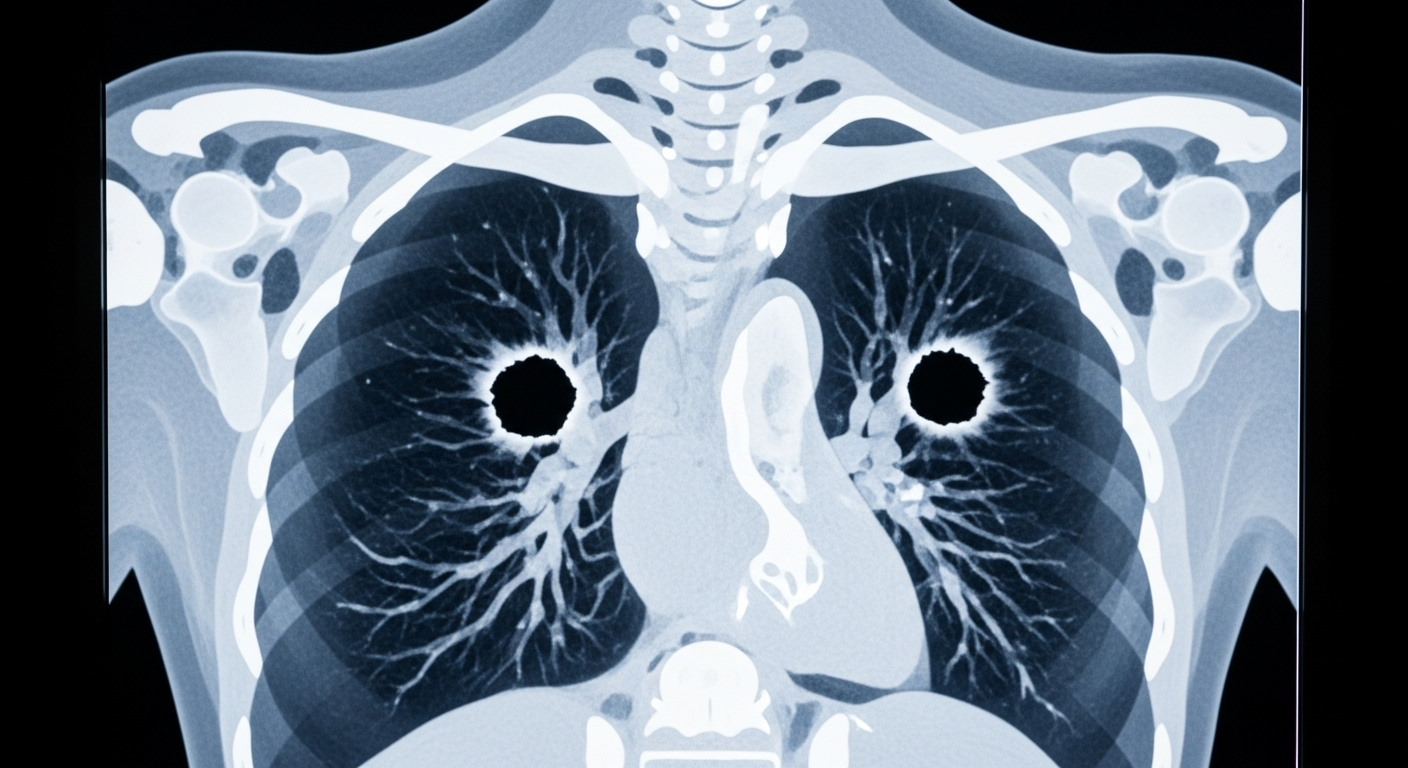

Les problèmes de santé de Dylan ont commencé à s’aggraver en 2021, lorsqu’un scanner a révélé deux trous dans ses poumons. Mais c’est à la mi-2024 que la situation est devenue dramatique : le nombre de trous est passé à 72. ‘J’ai découvert en juillet de l’année dernière à quel point les choses étaient devenues graves’, a raconté sa sœur, Caitlyn, au Daily Australian Mail. C’est à ce moment-là qu’il a été hospitalisé pendant trois semaines après avoir craché du sang. Son médecin lui a dit que s’il n’était pas venu si tôt, il serait mort. Malgré un traitement lourd qui ‘remplissait un sac à dos entier’, son état n’a cessé de se détériorer. Il est décédé le 15 mars, cinq jours seulement après que sa mère l’ait ramené à la maison pour organiser des soins palliatifs.

Bien que la cause exacte n’ait pas été rendue publique, la description de la maladie de Dylan correspond à une forme particulièrement agressive de pneumonie bactérienne appelée pneumonie nécrosante. Dans cette maladie, les bactéries et la réponse immunitaire du corps ne se contentent pas d’enflammer les poumons : elles tuent et liquéfient littéralement le tissu pulmonaire, laissant derrière elles des cavités, des ‘trous’. Ces trous peuvent s’agrandir et fusionner, et les vaisseaux sanguins peuvent être détruits, ce qui explique pourquoi les patients se mettent à cracher du sang.